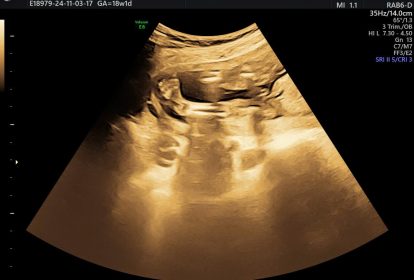

Vì vậy, để phòng ngừa bệnh bàn chân khoèo cho trẻ, mẹ cần có lối sống tích cực và chế độ dinh dưỡng phù hợp cho người đang mang thai. Ở tuần thứ 17 của thai kỳ có thể phát hiện được bàn chân khoèo thông qua siêu âm. Mẹ nên đi khám thai định kỳ, thực hiện siêu âm định kỳ để biết được tình trạng phát triển của thai nhi, kịp thời phát hiện và tìm hướng xử lý tốt nếu có các bất thường xảy ra.